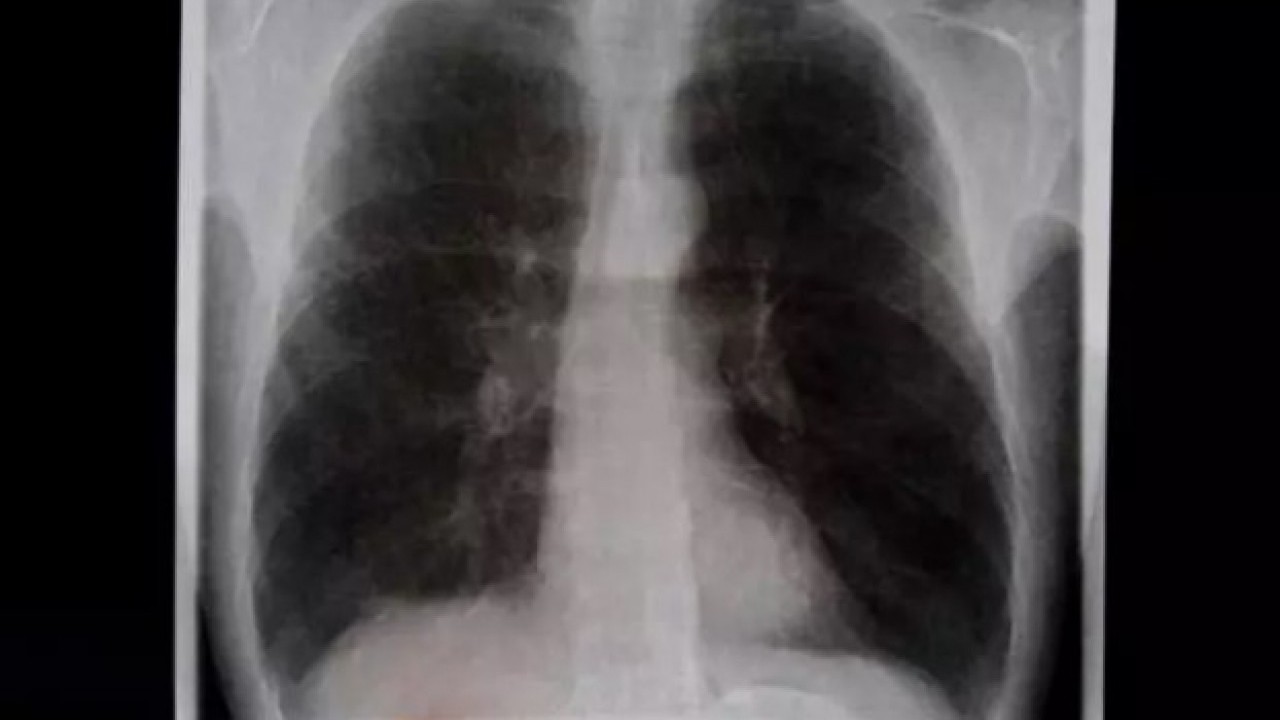

Türkiye'deki sigara kullanımında kadınların erkekleri geçmesi sonrası Ülkemizde kadınların sigara kullanımının erkekleri geçmesinin ardından Prof. Dr. Toker Ergüder, akciğer sağlığı açısından kadınları uyardı. Kadınlarda sigara kullanımının 15-24 yaş arası kadınlarda yüzde 90’a ulaşması üzerine Ergüder, önümüzdeki 10 yıl içinde kadınlar arasında akciğer kanseri salgınının ortaya çıkabileceğini söyledi.

"10 YIL İÇİNDE KADINLAR ARASINDA AKCİĞER SALGINI ÇIKACAK" Bir yandan Türkiye'de sigara içme oranları artarken, bir yandan da endüstrinin yeni bir ürünü piyasaya sokmaya çalıştığını belirten Prof. Dr. Ergüder, "Bu da elektronik ve sıvı sigaralar. Bu ürünlerin Türkiye'deki satışları yasak. Bununla ilgili çok sıkı kanunlarımız var ama kaçak yollarla giriyorlar piyasaya. Zaten Türkiye'de genç kadınlarda sigara içme oranları artıyor. Ne yazık ki üzülerek söylüyorum önümüzdeki 10 yıl içinde kadınlar arasında da bir akciğer kanseri salgını ortaya çıkacaktır" dedi./ kaynak: haber7